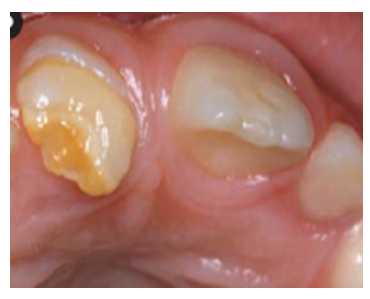

Oštećenja u gleđi zuba u razvoju(dok još nije iznikao) mogu da izazovu i lokalni uzroci. To su najšešće utisnuće mlečnog zuba ili infekcija u kosti oko obolelog mlečnog zuba. Tada se razvojno oštećenje gleđi javlja na stalnom zubu. (Slika 3.)

Slika 3. Stalni sekutići(desno) je povređen od strane mlečnog zuba u toku razvoja tako da je izostala izgradnja gleđi